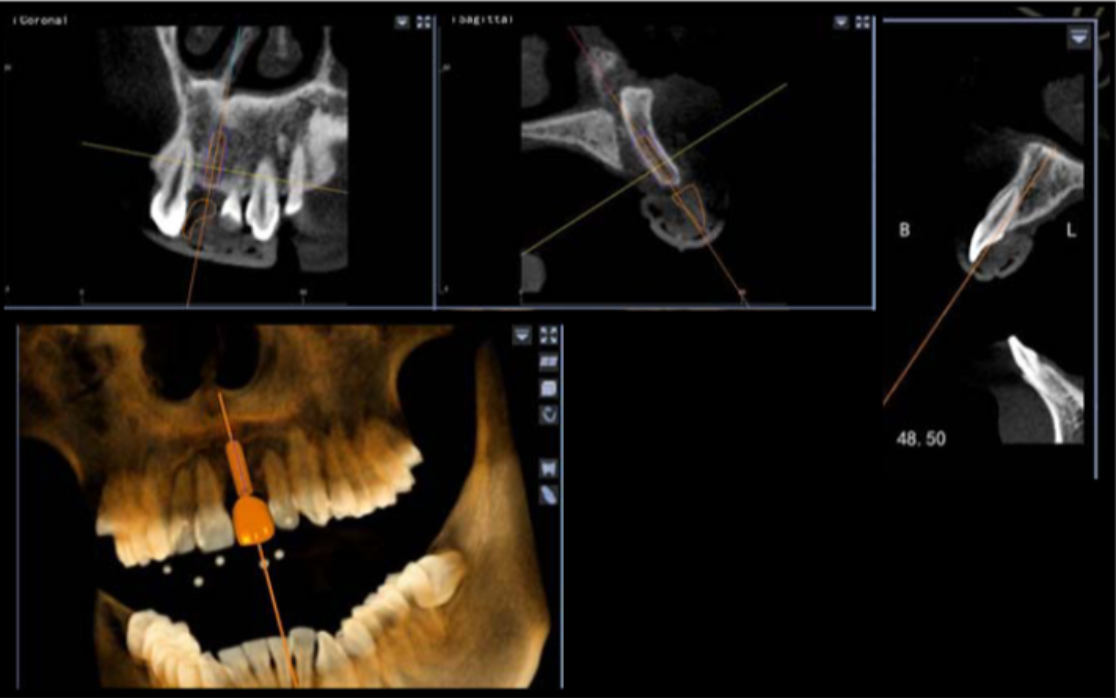

此病例中主刀醫(yī)生借助迪凱爾數(shù)字化口腔種植手術(shù)導(dǎo)航系統(tǒng),精確的控制每鉆的定點(diǎn)精度和角度,保證了每次制備定點(diǎn)誤差小于0.4mm,角度偏差不大于3.5°,極大的保證了種植體按照種植前的手術(shù)設(shè)計(jì)就位。